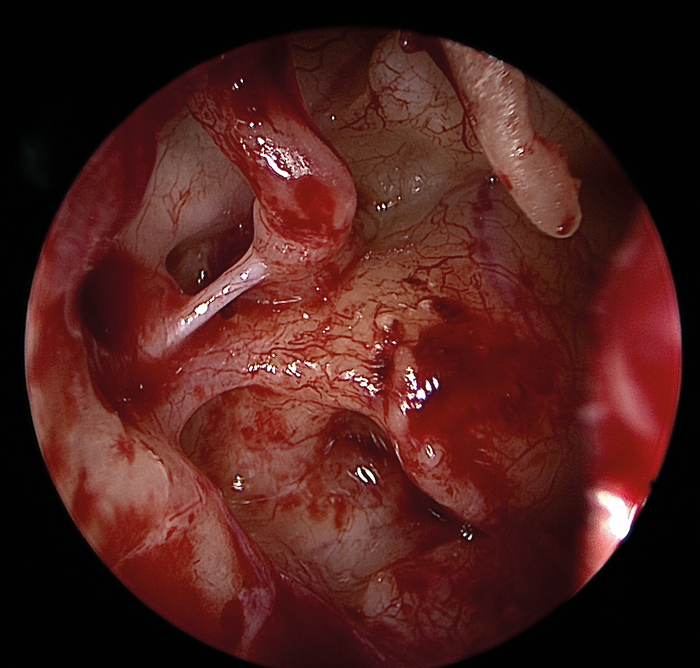

The greatest benefit of the endoscope lies in exposing previously hidden areas or blind spots such as the retrotympanum, hypotympanum, anterior mesotypanum, epitympanum and antrum (Figure 4).

Figure 4 (Top, middle and bottom): Endoscopic view of the middle ear with an intact ossicular chain.